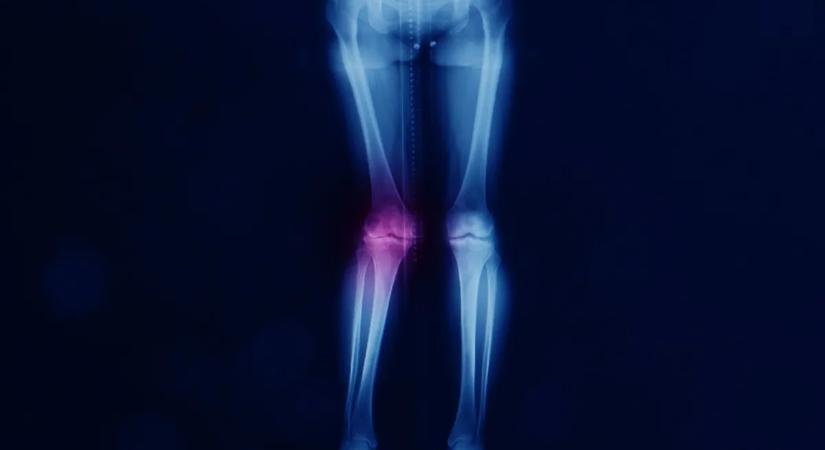

Valgus lábállás: amikor az X-lábúság több mint esztétikai kérdés

Az X-lábúság sokáig panaszmentes lehet.